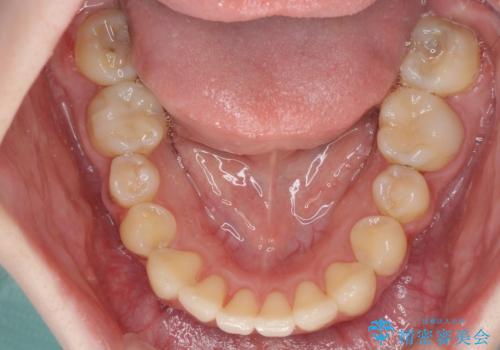

デコボコ歯列をきれいに インビザラインによる矯正治療

主に下顎歯列全体の後方移動とIPR(歯と歯の間を削る)によってデコボコが解消するように設計し、インビザラインにより治療を行うこととしました。

奥歯の知覚過敏が顕著となり、その影響で奥歯の咬み合わせ改善のための顎間ゴムの装着ができず、咬合を仕上げるまでに長い期間を要することとなりました。